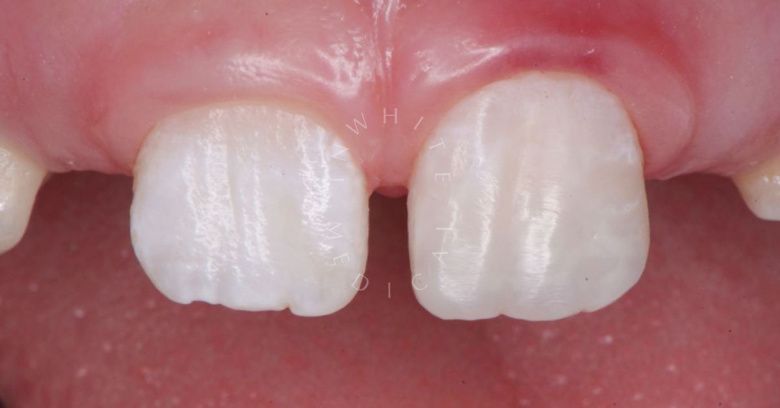

Стоматология Москва лучшие клиники. Лечение фиссурного кариеса под увеличением - до процедуры

До После